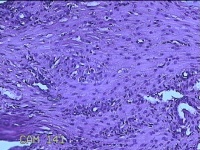

宫腔粘连带

标本名称

大体所见

灰白暗红色不规则碎组织1.3x1.2x0.3cm一堆。

图2